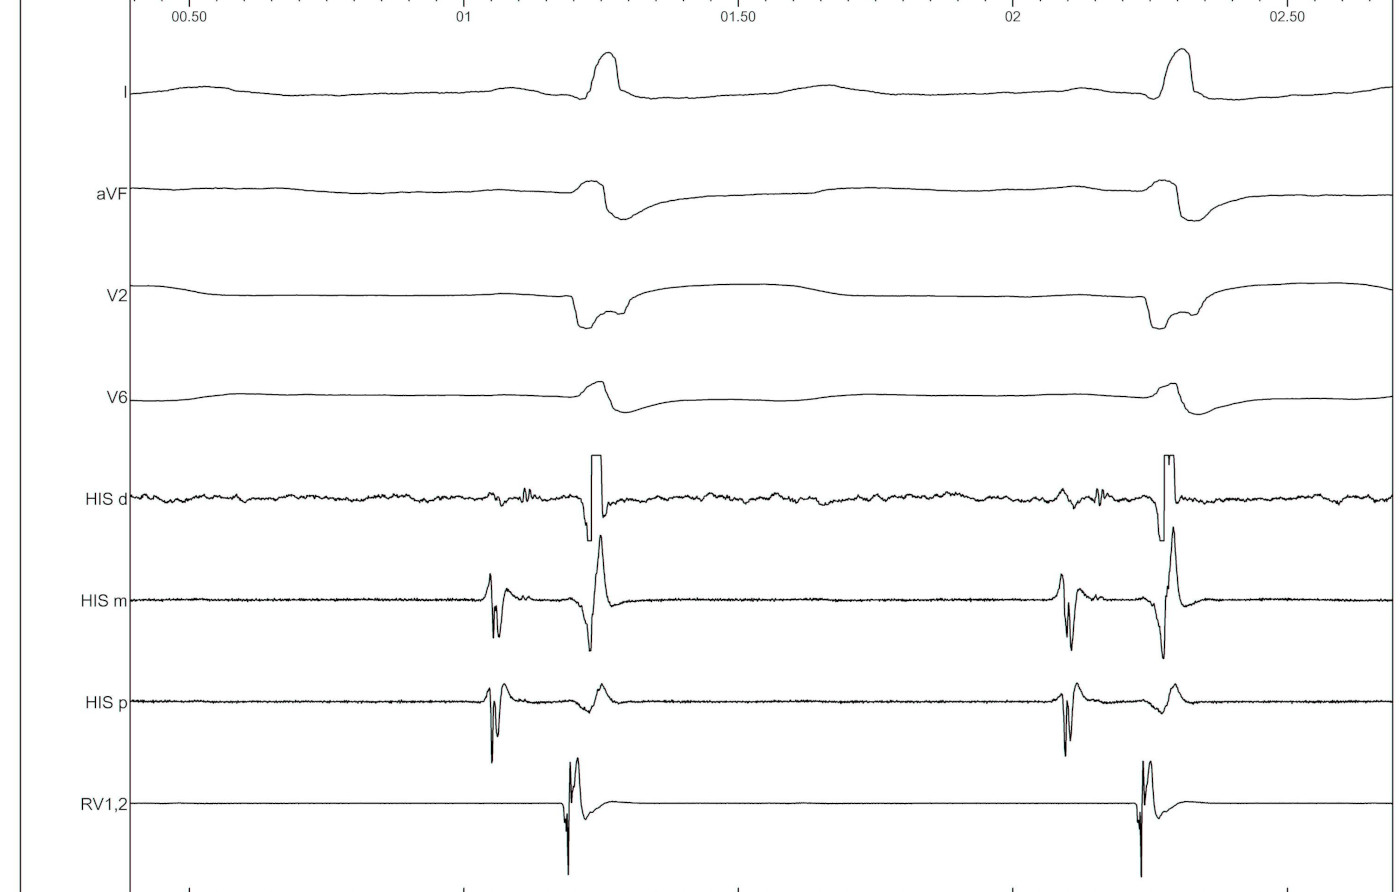

Intracardiac

02_baseline_IC.jpg